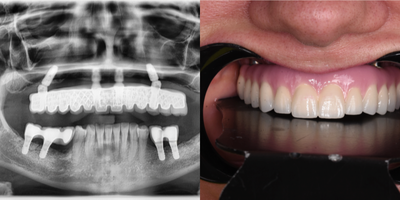

18-24 year old woman treated with All-on-4 Dental Implants, Dental Implants

A 23 years old lady had lost her teeth and only hopeless roots were present at the beginning. Although there were bone resorption at posterior maxilla and posterior mandible.An All-on-4 implant treatment was decided according to 3D CT. All teeth have been extracted and implants have been placed. An immediate temporary prosthesis has been delivered just after the surgery and patient was recommended to consume soft diet during 3 months of healing phase.In the end of 3 months, permanent ceramic prostheses were delivered. An aesthetic smile design protocol was performed to achieve ideal proportions in the permanent prostheses.